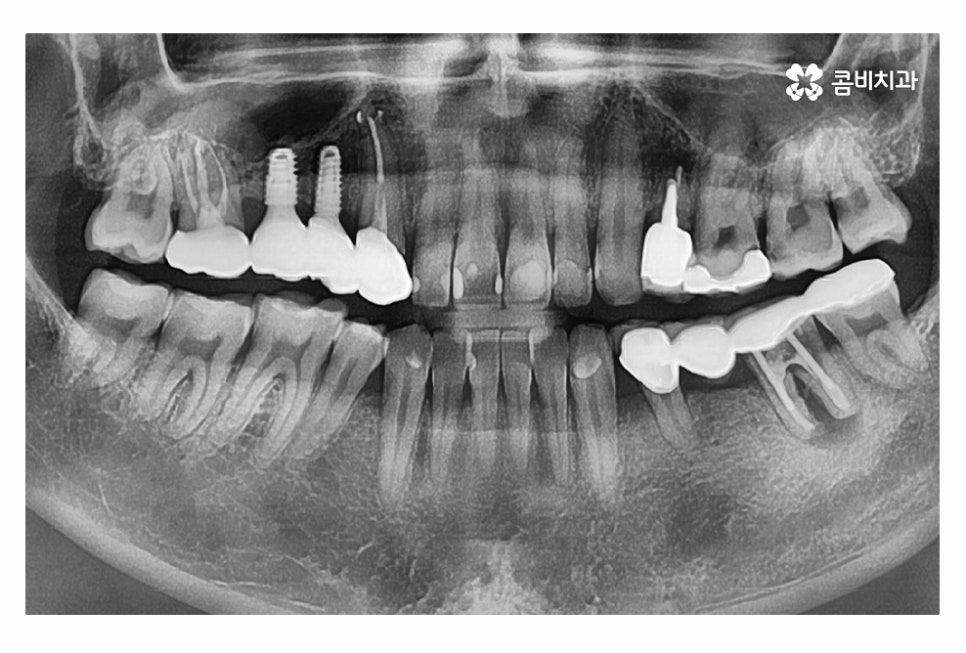

그리고 임플란트의 재료도 수명 관리에 중요하니 단지 저렴한 곳을

선택하는 것이 아니라 장기적인 관점으로 하나하나 철저하게 따져보실 필요가 있는데요.

요즘은 20대임플란트 치료에 대해 원데이임플란트가 많이 알려져 있긴 하지만

개개인에게 적합한 치료 계획은 달라질 수 있기 때문에

치과에서 먼저 정확한 정밀검진을 받아보시길 권해드리고 있어요.

치아를 잃고 임플란트 치료를 곧바로 해야 하며 그대로 방치하게 될 경우에는

잇몸이 점점 흡수되며 치열이 망가질 우려가 있고

소화불량 및 턱관절 장애 등 치아의 문제가 전신 건강에도

안좋은 영향을 줄 수 있으니 주의해야 할 필요가 있어요